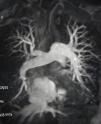

CTEPH should also be suspected at the time of acute PE when CTPA shows findings suggestive of chronic fibrothrombotic deposits – bands, webs, arterial narrowing or retraction, and/or dilated bronchial arteries (Figure 5) – or when the echocardiogram depicts an estimated PASP >60 mmHg and/or features of RV dysfunction and hypertrophy.14 In asymptomatic patients with risk factors (Figure 1) or a high CTEPH prediction score (Table 1),20 diagnostic assessment should also be considered.2 A proposed diagnostic algorithm is shown in Figure 6. Initial assessment of patients with suspected CTEPH should include a transthoracic echocardiogram to determine the probability of PH (Table 2) and a V/Q scan to look for mismatch perfusion defects.2 In general, especially considering that CTPA performed by chest radiologists is not widely accessible, a V/Q scan remains the gold standard exam for exclusion of CTEPD without PH at rest, due to its high sensitivity (96.2–97.4%) and negative predictive value of almost 100%47,48 (Figure 7). Other perfusion techniques, such as dual-energy CT scan or magnetic resonance perfusion, may be superior to a V/Q scan (Figure 8). However, these are more technically challenging and expensive, have limited availability, and lack multicenter validation.3

Magnetic resonance imaging angiogram demonstrating chronic thromboembolic pulmonary hypertension in an operable distribution, affecting the right middle and lower lobes as well as the left lower lobe. There is also evidence of tricuspid regurgitation with retrograde flow of contrast into the hepatic veins.